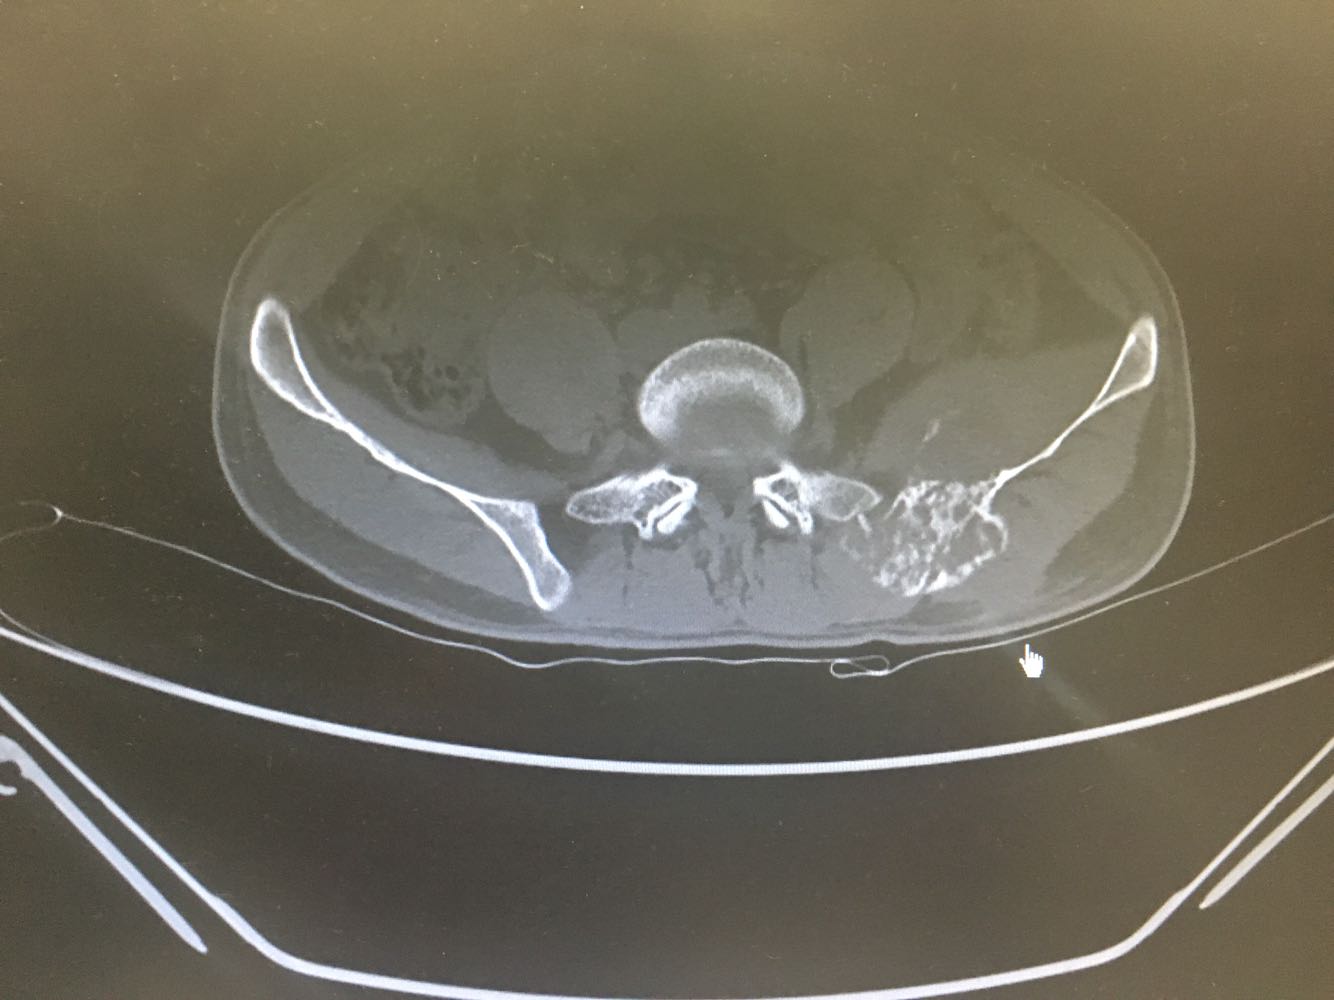

患者,男性,28岁 主诉:左髂疼痛3月 现病史:患者于3月前无明显诱因出现左髂疼痛,行走时加重,休息后缓解,未予重视,1月前发现左腰骶部一质硬肿块,遂至我院门诊就诊,查骨盆X片示:左髂骨骨质改变,现为进一步诊治收治入院,发病以来,神清,精神可,胃纳夜眠可,二便无殊,体重无明显变化。

诊断:髂骨肿瘤(左侧) 治疗:进一步完善相关检查后行活检明确诊断,考虑恶性肿瘤。